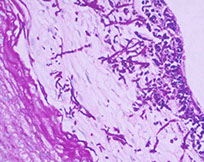

Should be considered in immunocomp pts c odynophagia and presence of bacteria w/o fungi or ca seen

- may be cause of occult sepsis